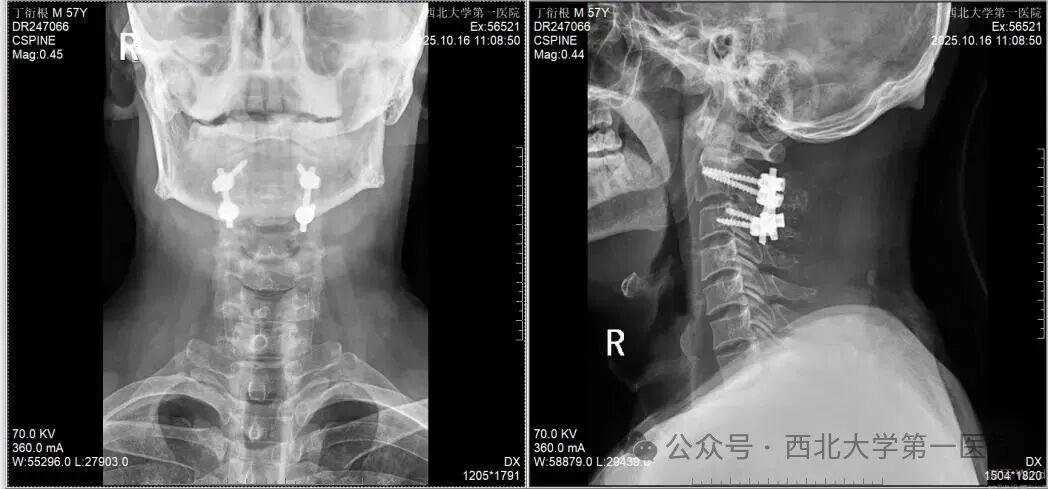

手术团队借助术前三维CT规划数据,结合术中C型臂X光机多次透视定位,精准操作。最终,四枚长度、直径均经过精密计算的螺钉,完美植入C2椎弓根及C3侧块预定位置,成功避开了椎动脉和脊髓。安装连接棒后,术中透视显示:颈椎生理曲度恢复,骨折复位满意,内固定位置精准无误。全场人员悬着的心终于落下,手术取得圆满成功。

在医护人员的精心照料下,患者未出现任何神经并发症,颈部疼痛显著缓解,目前正在顺利康复中。术后颈椎DR显示,内固定物位置良好。